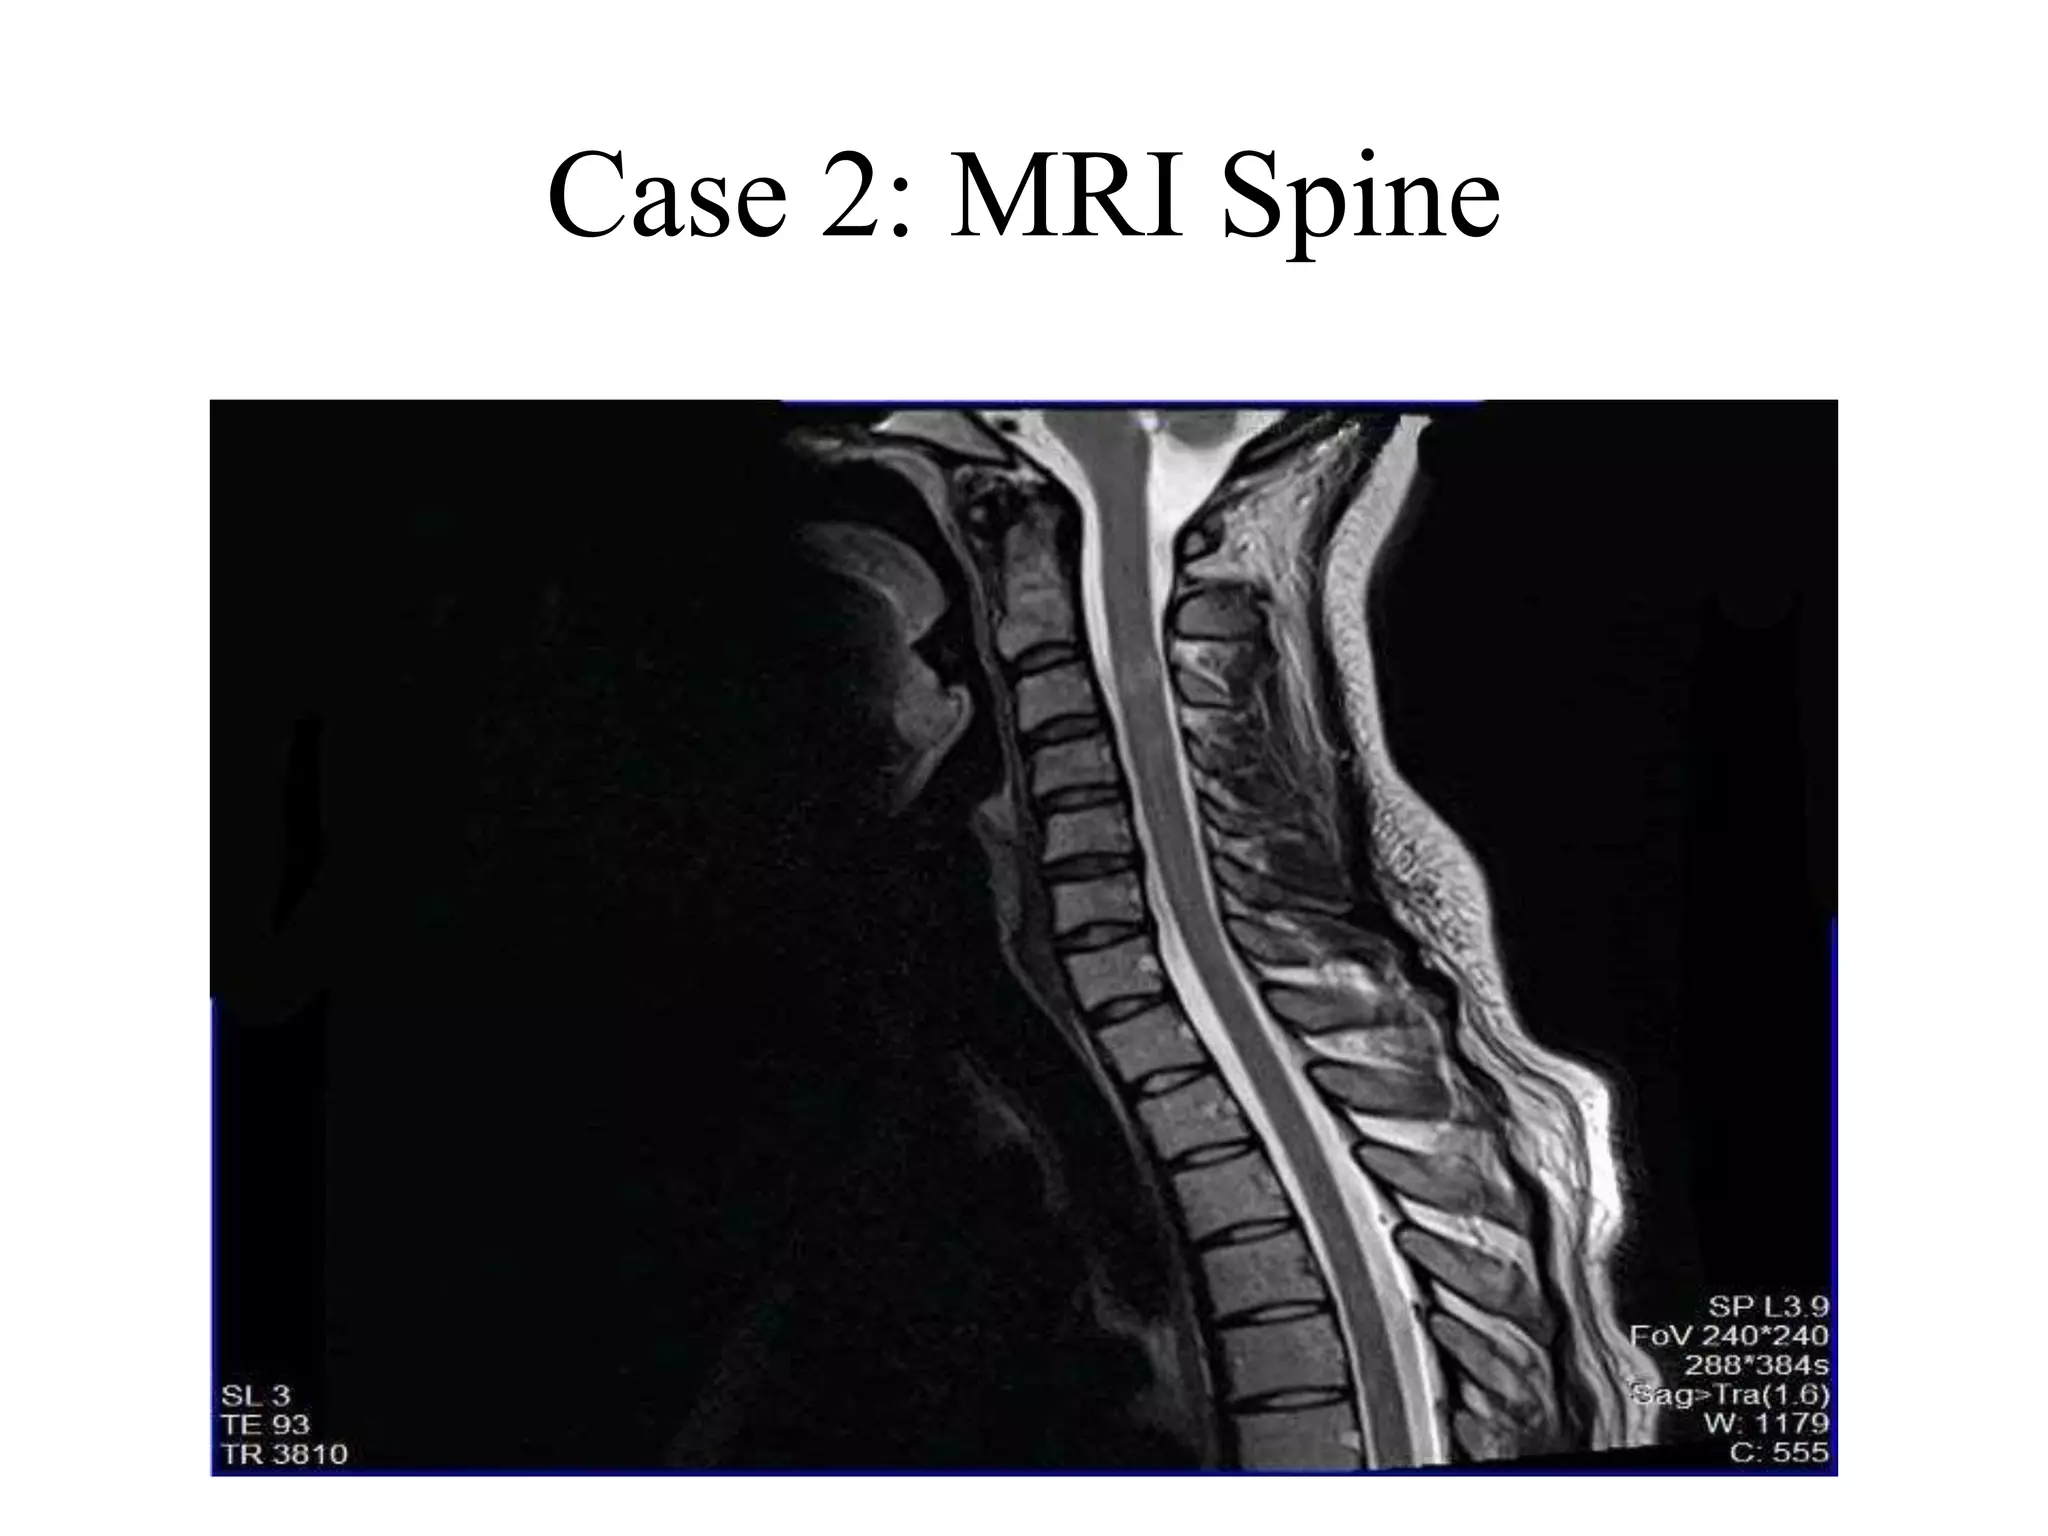

Case 2: MRI Spine

Case 2

• Mr. A.M.J is a 33 years old Kuwaiti male, diagnosed to

have MS in 2008.

• In Jan 2008, he developed diplopia, followed by

paresthesia in feet, ascending to abdomen, chest and

forearms.

• These symptoms persisted

• By June 2008, he was ataxic and on a wheel chair,

when he sought medical advice

• MRI was consistent with MS

• Marked imrovement was noted in sensory symptoms

after pulse steroids.

Case 2: MRI Brain 2

Case 2: MRI Cervical spine 2

• MRI showed marked worsening, with

tumefactive enhancing lesions

• A CSF study was done, which was normal,

negative for JCV.

• Considering this as a failure of Tysabri, it is

planned to treat him with Rituximab